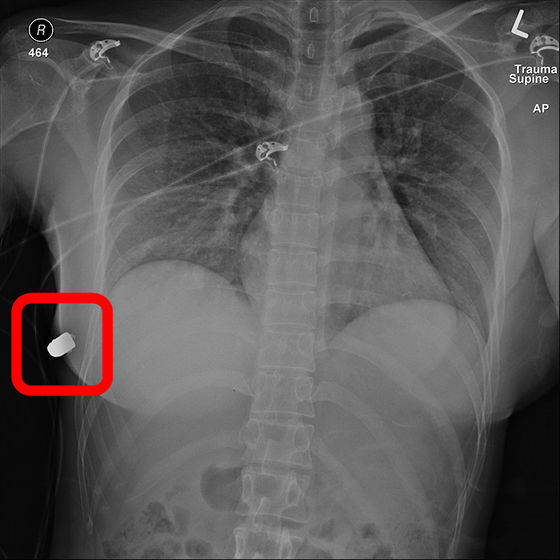

弾痕の存在した左胸側とは逆の右胸側の皮下に弾丸のようなかたまりの存在が確認できました。被害者の胸部のレントゲン写真が以下。右胸側側面に存在する影が弾丸そのものであることがハッキリとわかります。

左胸の弾痕から右胸にかけてガスのような軌跡が残されていることから、「左胸乳頭上部から入射した弾丸が

シリコン樹脂によって偏向して、体内を通過して右胸で止まった」と推定されました。また、レントゲンによって、

肋骨が骨折しており、さらに肺挫傷を生じているものの、胸腔内に損傷は生じていないことがわかりました。行われた外科手術によって、両胸のシリコン樹脂が除去され、弾丸が摘出されました。以下が右胸側のシリコン樹脂。